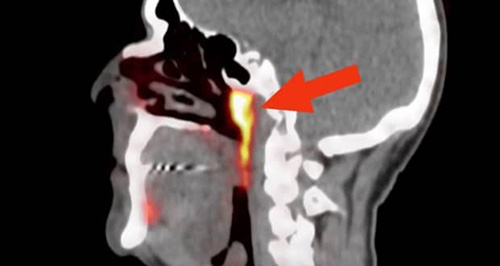

پژوهشگران هلندی زمانی که مشغول بررسی وضعیت بیماران مبتلا به سرطان پروستات بودند، مقداری گلوکوز رادیواکتیو را به بدن این افراد تزریق کردند. چنین روشی در کنار استفاده از اسکن PSMA PET/CT میتواند محل دقیق تومورها در بدن انسان را مشخص کند؛ اما در کمال تعجب، ماده مورد نظر در قسمت دیگری از بدن و جایی که کسی انتظار آن را نداشت، ظاهر شد. دانشمندان مشاهده کردند که گلوکز رادیواکتیو به کار رفته پشت قسمت بالایی حلق را نورانی کرده بود.

قسمتهای نارنجی رنگ عکس بالا سایر غدههای بزاقی سر هستند و بخشی که با فلشهای آبی نشان داده شده، همان عضو جدید و مرموز بدن است. وتر ووگل (Wouter Vogel) از موسسه سرطان هلند میگوید که بدن انسان شامل سه جفت غده بزاقی بزرگ میشود، اما هیچکدام از این جفتها در پشت قسمت بالایی حلق قرار ندارند.

در مورد دلیل این مسئله که چرا تاکنون وجود غدههای مورد نظر توجه پزشکان و متخصصان را به خود جلب نکرده، ووگل و تیمش میگویند که به احتمال قوی محل قرارگیری این اندام در قسمت پایینی جمجمه باعث شده تا از لحاظ دسترسی تجهیزات آندوسکوپی، محدودیتهایی جدی برای رسیدن به این محل وجود داشته باشد. ممکن است که مجراهای بزاقی این غدهها در گذشته شناسایی شدهاند، اما هیچ دانشمندی متوجه این موضوع نشده بود که این مجراها جزو یک سیستم ترشح بزاق بزرگتر هستند.

با این حال دسترسی به تجهیزات پیشرفتهای مانند اسکن PSMA PET/CT باعث شده تا محققان توانایی گذر کردن از محدودیتهای سایر تجهیزات مانند سی تی اسکن، ام آر آی و وسایل التراسونیک را داشته باشند. این تجهیزات قدیمیتر از لحاظ دیداری ما را محدود میکنند و خوشبختانه میبینیم که با پیشرفت علم و ساخت دستگاههای جدید، قابلیتهایی نوین برای بررسی بدن انسان به وجود آمدهاند.